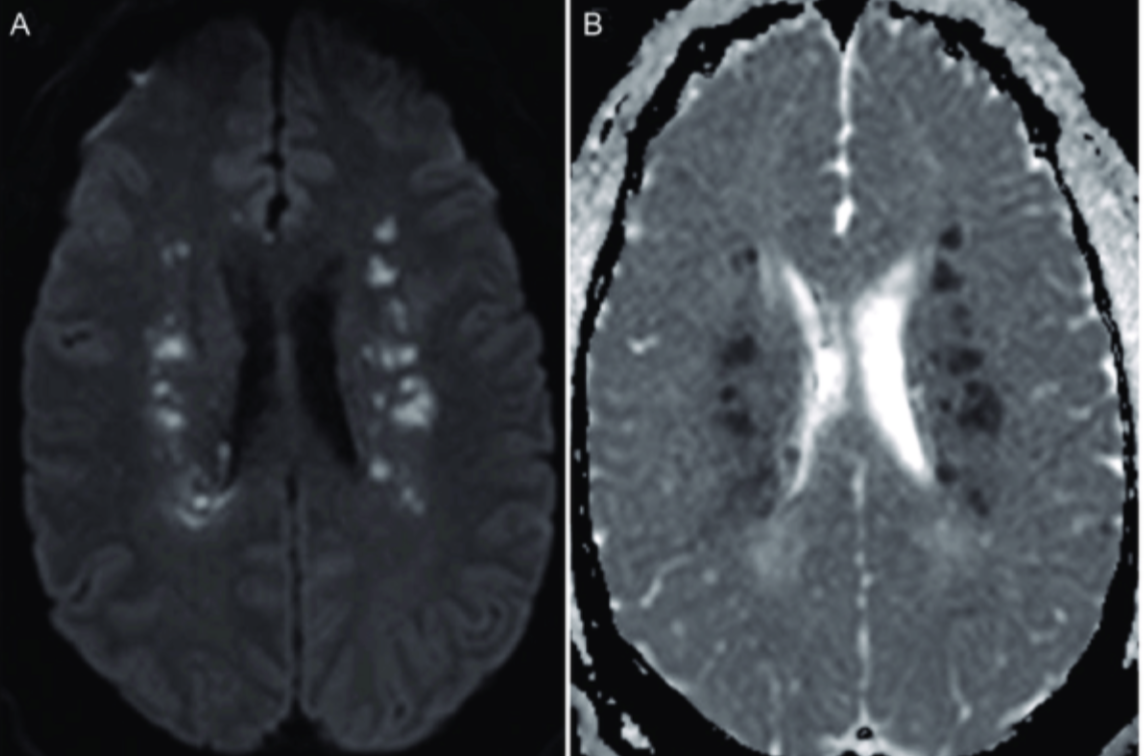

Thalamic stroke (aka Lacunar Strokes (means “little lake”)) is a _____ etiology.

hypertensive

Thalamic stroke sensory deficits (aka Pure sensory stroke or lacunar stroke syndrome) & nuclei involved.

Thalamocapsular stroke (aka sensorimotor stroke or lacunar stroke syndrome) is combined ____ deficits. Damage to the ____ (2).